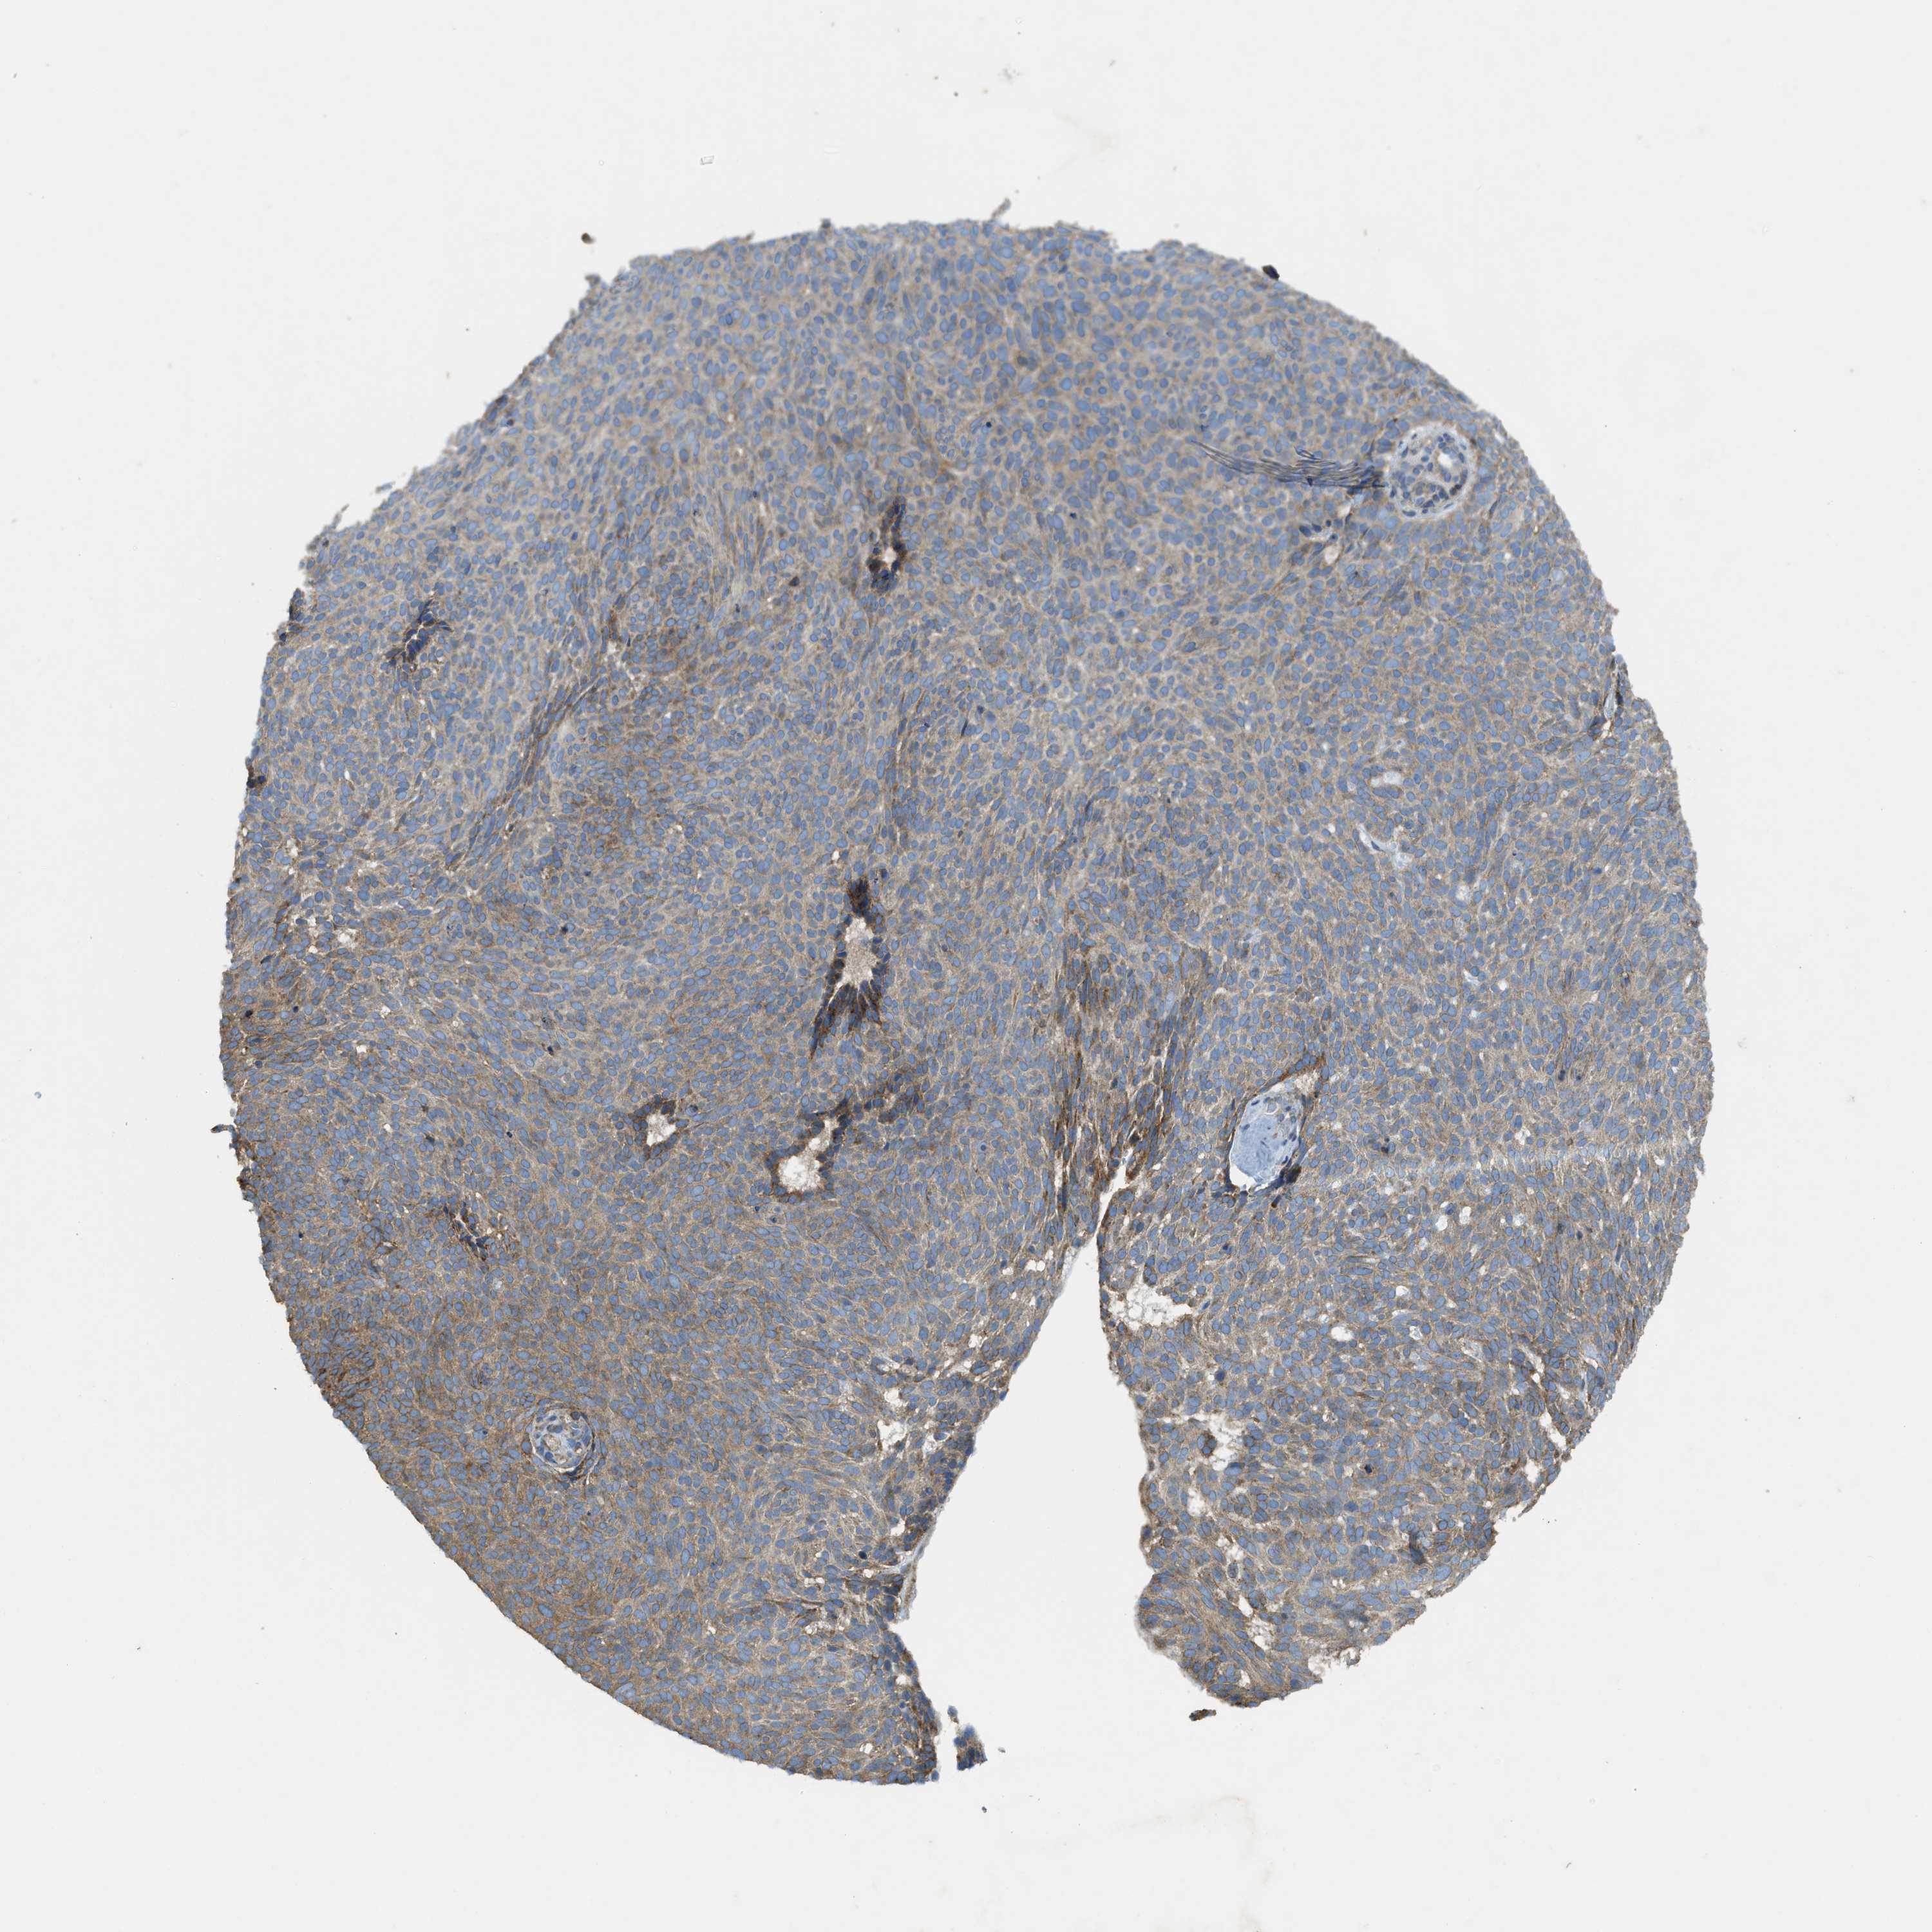

SKIN CANCER - Protein expressioni

A mouse-over function shows sample information and annotation data. Click on an image to view it in a full screen mode. Samples can be filtered based on level of antibody staining by selecting one or several of the following categories: high, medium, low and not detected. The assay and annotation is described here.

Antibody stainingi

Antibody staining in the annotated cell types in the current human tissue is reported as not detected, low, medium, or high, based on conventional immunohistochemistry profiling in selected tissues. This score is based on the combination of the staining intensity and fraction of stained cells.

Each image is clickable and will lead to virtual microscopy that enables deeper exploration of all samples and also displays staining intensity scores, fraction scores and subcellular localization as well as patient and tissue information for each sample.

Antibody HPA018216

Antibody HPA019173

Staining

High

Medium

Low

Not detected

Intensity

Strong

Moderate

Weak

Negative

Quantity

>75%

75%-25%

<25%

None

Location

Nuclear

Cytoplasmic/membranous

Cytoplasmic/membranous,nuclear

Squamous cell carcinoma in situ, NOS

Squamous cell carcinoma, NOS

Squamous cell carcinoma, metastatic, NOS

Basal cell carcinoma